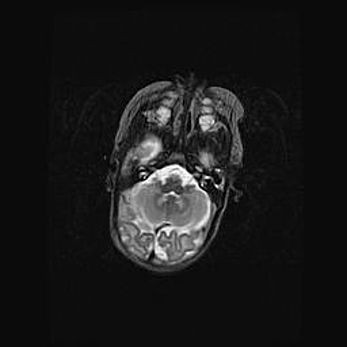

Лейкомаляция с кистозно-глиозной дегенерацией головного мозга.

Возраст: 2 месяца 25 дней

Вес: 6400 г

Окружность головы: 40 см

Срок гестации: 41 неделя

Лейкомаляцию относят к ишемически-гипоксическим повреждениям головного мозга, диагностируемым у новорожденных. При лейкомаляции в головном мозге обнаруживают очаги некроза, возникшие после тяжелой гипоксии и нарушения кровотока. В процессе морфогенеза очаги проходят три стадии: 1) развития некроза, 2) резорбции и 3) формирования глиозного рубца или кисты. Перивентрикулярная лейкомаляция (ПЛ) встречается примерно в 12% случаев среди новорожденных, обычно – у недоношенных детей, причем, частота ее зависит от массы, с которой младенец появился на свет. Наибольшее число малышей страдает лейкомаляцией, если масса при рождении 1500-2500 г.